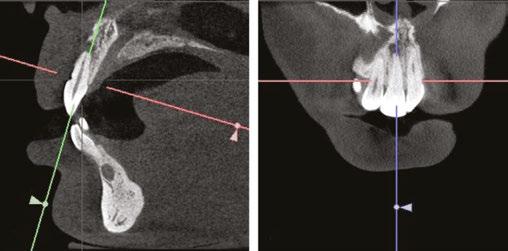

A CBCT X-ray was captured to further investigate and compare which mandibular anterior teeth were most compromised, as well as better visualize any pathologies that may be present (when compared to a panoramic X-ray, Figure 3). When visualizing individual teeth, crosshairs in the 3D imaging software were centered in each orthogonal direction to ensure image accuracy and reproducibility. The image is adjusted to view all teeth either parallel or perpendicular to its axis making sure that the evaluations are accurate in comparing each tooth and its supporting bone.

The CBCT image revealed several findings. First, it was apparent that a periapical radiolucency (PARL) existed in association with the overlapping mandibular incisors (Figures 4A – 4C). Figure 4A shows tooth No. 24 with compromised facial alveolar support, while figure 4C shows tooth No. 25 with a greater amount of visible facial bone. In figure 4E, tooth No. 27 is proclined and has compromised facial alveolar support. Lastly, a second PARL was noted surrounding tooth No. 8 (Figure 5).

Treatment plan

The established treatment plan and extraction recommendation for this patient was primarily based on the CBCT image findings with regards to alveolar support and space analysis. It was clear that tooth No. 24 had the least alveolar support and was already experiencing gingival stripping. However, extraction of this tooth alone would not provide enough space to relieve the crowding, as it is already entirely blocked out of the arch. If one were to extract tooth No. 28 also, tooth No. 27 would need to be distalized and retracted into the arch to allow room for the alignment of the remaining incisors. A potentially more efficient plan would be to extract the periodontally compromised tooth No. 27, as its root is already significantly dehisced thru the facial cortical plate making room for proper alignment of tooth No. 26. Therefore, the final treatment plan for this patient is as follows: refer to general dentist or endodontist for evaluation of PARLs on tooth No. 8 and No. 25 (Figures 4A, 5A, and 5B) and extraction of Tooth Nos. 5, 12, 24, and 27 (Figures 6A and 6B).

Figure 3: Panoramic X-ray taken with diagnostic records on December 17, 2020 Figures 5A-5B: 5A. Shows the sagittal view of tooth No. 8 with associated PARL. 5B. Shows the coronal view of tooth No. 8 with associated PARL Figures 6A-6B: 6A. Shows extractions of tooth Nos. 5 and 12. 6B. Shows extractions of tooth Nos. 24 and 27 Figures 4A-4D: 4A. Shows the sagittal view of tooth No. 24 with what appeared to be an associated PARL. Figure 4B shows the PARL from an axial view centered in the mandibular anterior region. Figure 4C shows tooth No. 25 in the sagittal view, closely associated with the PARL. Figure 4D shows the 3D model of the maxillary and mandibular arches. Figure 4E shows tooth No. 27 in the sagittal view A. B. D. C. E. A. A. B. B.